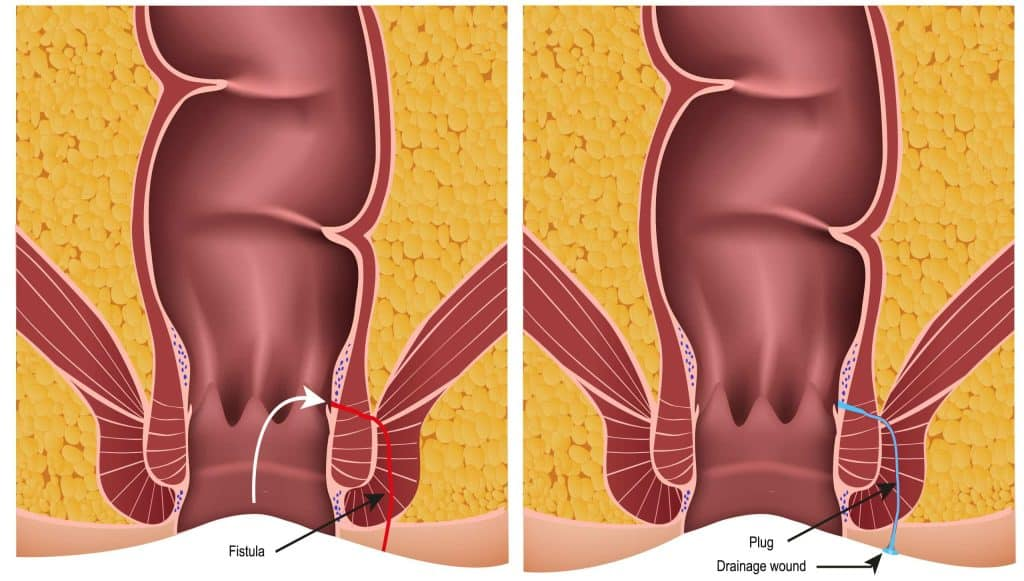

An anal fistula is unlike a simple infection or swelling that can go away with antibiotics or home remedies